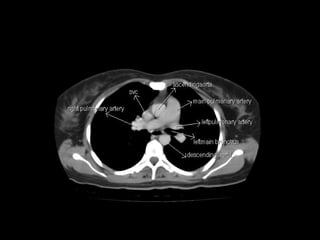

Radiographers use medical imaging equipment like X-rays and MRIs to produce images of patients' internal structures and organs. They are responsible for positioning patients, operating scanning machines, and ensuring quality images. Radiographers must have strong attention to detail, excellent communication skills, and the ability to work well under pressure to accurately capture anatomical features and diagnose any abnormalities.